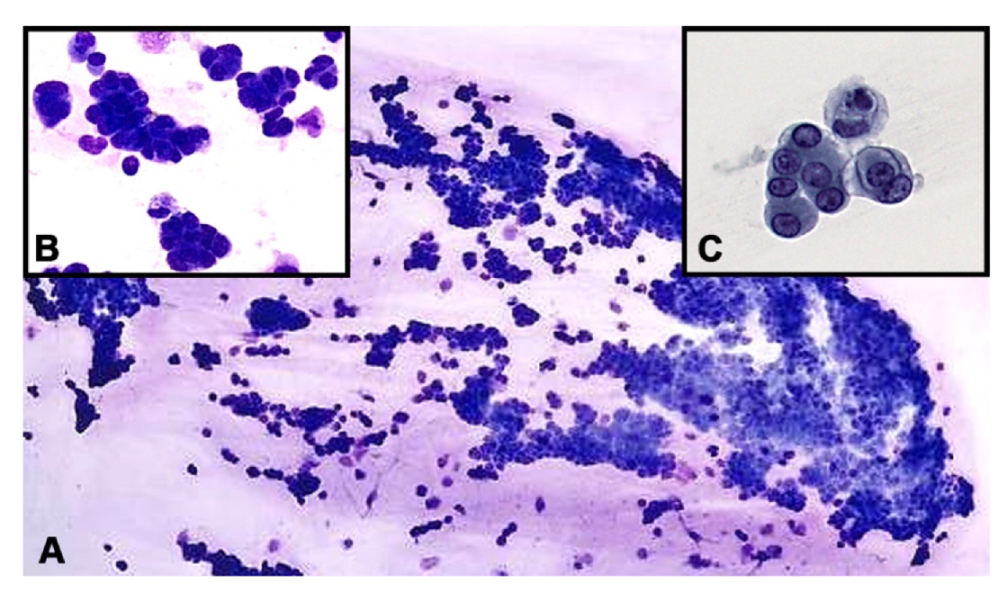

Microscopically, sheets of malignant epithelioid cells forming three dimensional groups were identified in the vitreous. Some groups appeared to form micropapillary structures with enlarged, hyperchromatic, eccentrically located nuclei with small nucleoli and a moderate amount of cytoplasm (Figure 2). Immunohistochemical studies were performed with appropriate positive controls, encompassing anti-cytokeratin cocktail AE1/AE3 (mouse monoclonal antibody; 1:100–1:500 dilution range; Cell Marque, Rocklin, CA, USA); PAX8 (mouse monoclonal antibody; 1:50–1:200 dilution range; Cell Marque, Rocklin, CA, USA), CD20 (mouse monoclonal antibody; 1:250 dilution; ThermoFisher Scientific, Riverside, CA, USA), CD3 (mouse monoclonal antibody; 1:10–1:20; ThermoFisher Scientific, Riverside, CA, USA), RCC (Human clear renal cell carcinoma antibody, mouse monoclonal antibody; 150–200 microliter; ThermoFisher Scientific, Riverside, CA, USA), SOX10 (rabbit polyclonal antibody; 1:25–1:100 dilute; Cell Marque, Rocklin, CA, USA) and S100 (mouse monoclonal antibody; 1–2 mg/mL; ThermoFisher Scientific, Riverside, CA, USA). All antibodies and testing were performed in a CLIA-certified laboratory.

Figure 2.

(A). Hypercellular vitreous fluid demonstrating sheets of cohesive malignant epithelioid cells (Diff-Quik stain. Original magnification ×100). Inset (B). Groups of tumor cells forming micropapilla-like structures (Diff-Quik preparation, ×400). Inset (C). Pap-stained smear depicting clusters of neoplastic epithelioid cells with eccentric nuclei and vacuolated cytoplasm (original magnification ×400).

The tumor cells were positive for AE1/AE3 and PAX-8 stains and were negative for CD20, CD3, RCC, SOX-10 and S-100 protein (Figure 3). A flow cytometry analysis indicated that there was no evidence of leukemia or lymphoma. The cytomorphologic features observed in the vitreous sample shared similarities with those seen in prior histopathologic sections of the nephrectomy specimens. The combined clinical, cytopathologic and immunohistochemical findings were consistent with metastatic carcinoma of renal cell origin.